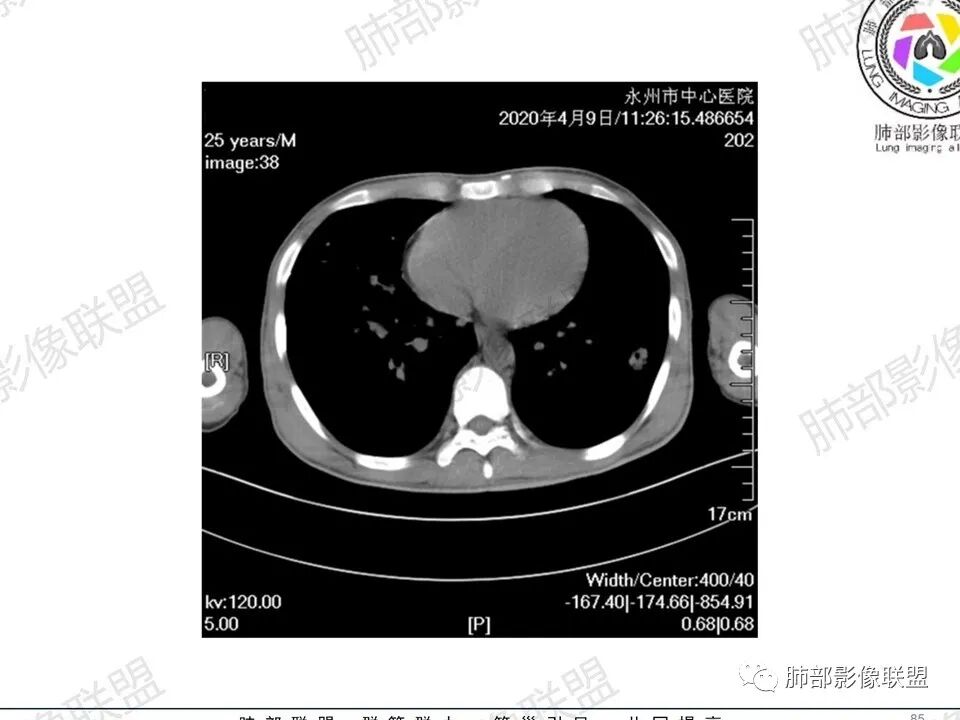

3、影像表现:双肺散在斑片影及结节影,部分结节内可见血管穿行,斑片影沿支气管血管束分布,近胸膜侧病变收缩不明显。部分中央淋巴间质增厚,小叶间隔增厚。病灶内支气管穿行,部分支气管略扩张。局部小结节呈串珠样改变。纵隔、肺门区、锁骨上及腋窝淋淋巴结肿大,部分有融合。心腔低密度。脾大。

5.双肺门及纵隔淋巴结显著增大,这改变相当显眼。这里强调“双肺门”及“多发”!

增大的淋巴结密度偏低且均匀。此外患者有体表淋巴结增大。

6.心腔密度减低。提示可能存在贫血。

1.临床表现明显,纵隔及双肺门淋巴结显著肿大,临床最为担心的还是淋巴瘤!

尤其患者有贫血及脾脏增大,又有体表淋巴结增大时,这也是临床相对常见的情形。

淋巴瘤肺部浸润表现多样,多发结节影是其最常出现的影像学改变,尤其是霍奇金病。

2.右肺多发微小结节影,部分沿血管束分布,尽管未见小叶间隔改变,但双肺门淋巴结增大确实应当首先排除结节病,但经验上说,结节病的增大淋巴结密度往往较高、较密实,边界往往清楚,“独立性”很强,绝无“融合之嫌”!此外,较少出现贫血、脾大,临床表现也往往较轻微。